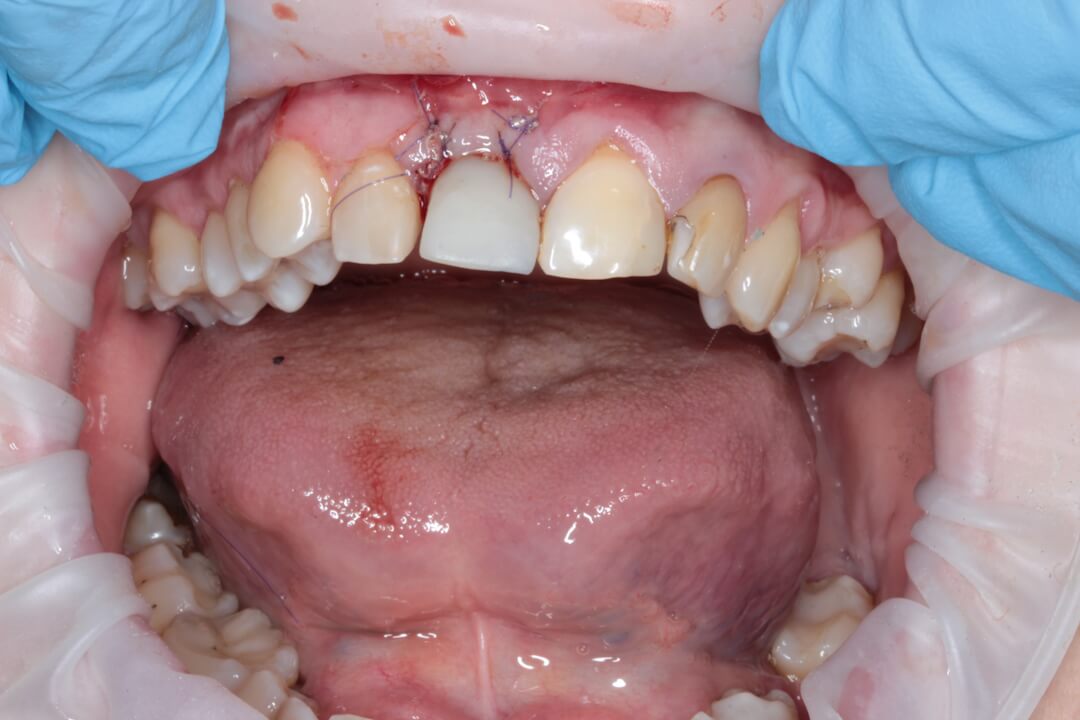

Рис. 1 Исходная ситуация.

Зуб был атравматически удален фрагментированием на части с помощью пьезохирургического аппарата и элеватора для максимального сохранения объема костной ткани в месте будущей дентальной имплантации. Во время экстракции врач сохранил целостность вестибулярной стенки альвеолы. Восстановление дефекта мягких тканей в данной области проводилось при помощи туннельной технологии субэпителиальным небным десневым трансплантатом . Устранение дефекта слизистой оболочки и десен способствует стабильному высокоэстетическому результату лечения. После этого хирург осуществляет наращивание костной ткани в вестибулярной области с использованием твердых частиц остеопластического материала. Для предотвращения попадания костного материала на внутреннюю часть имплантата врач устанавливает формирователь десны. Учитывая то, что пациентка по профессии учитель и впереди у нее было много ответственных мероприятий, было принято решение изготовить временную коронку на дентальный имплант непосредственно во время операции, так как все необходимые для этого условия были соблюдены и была такая возможность для этого.

Рис. 2. Вид пациентки после всех проведенных манипуляций в первое посещение.